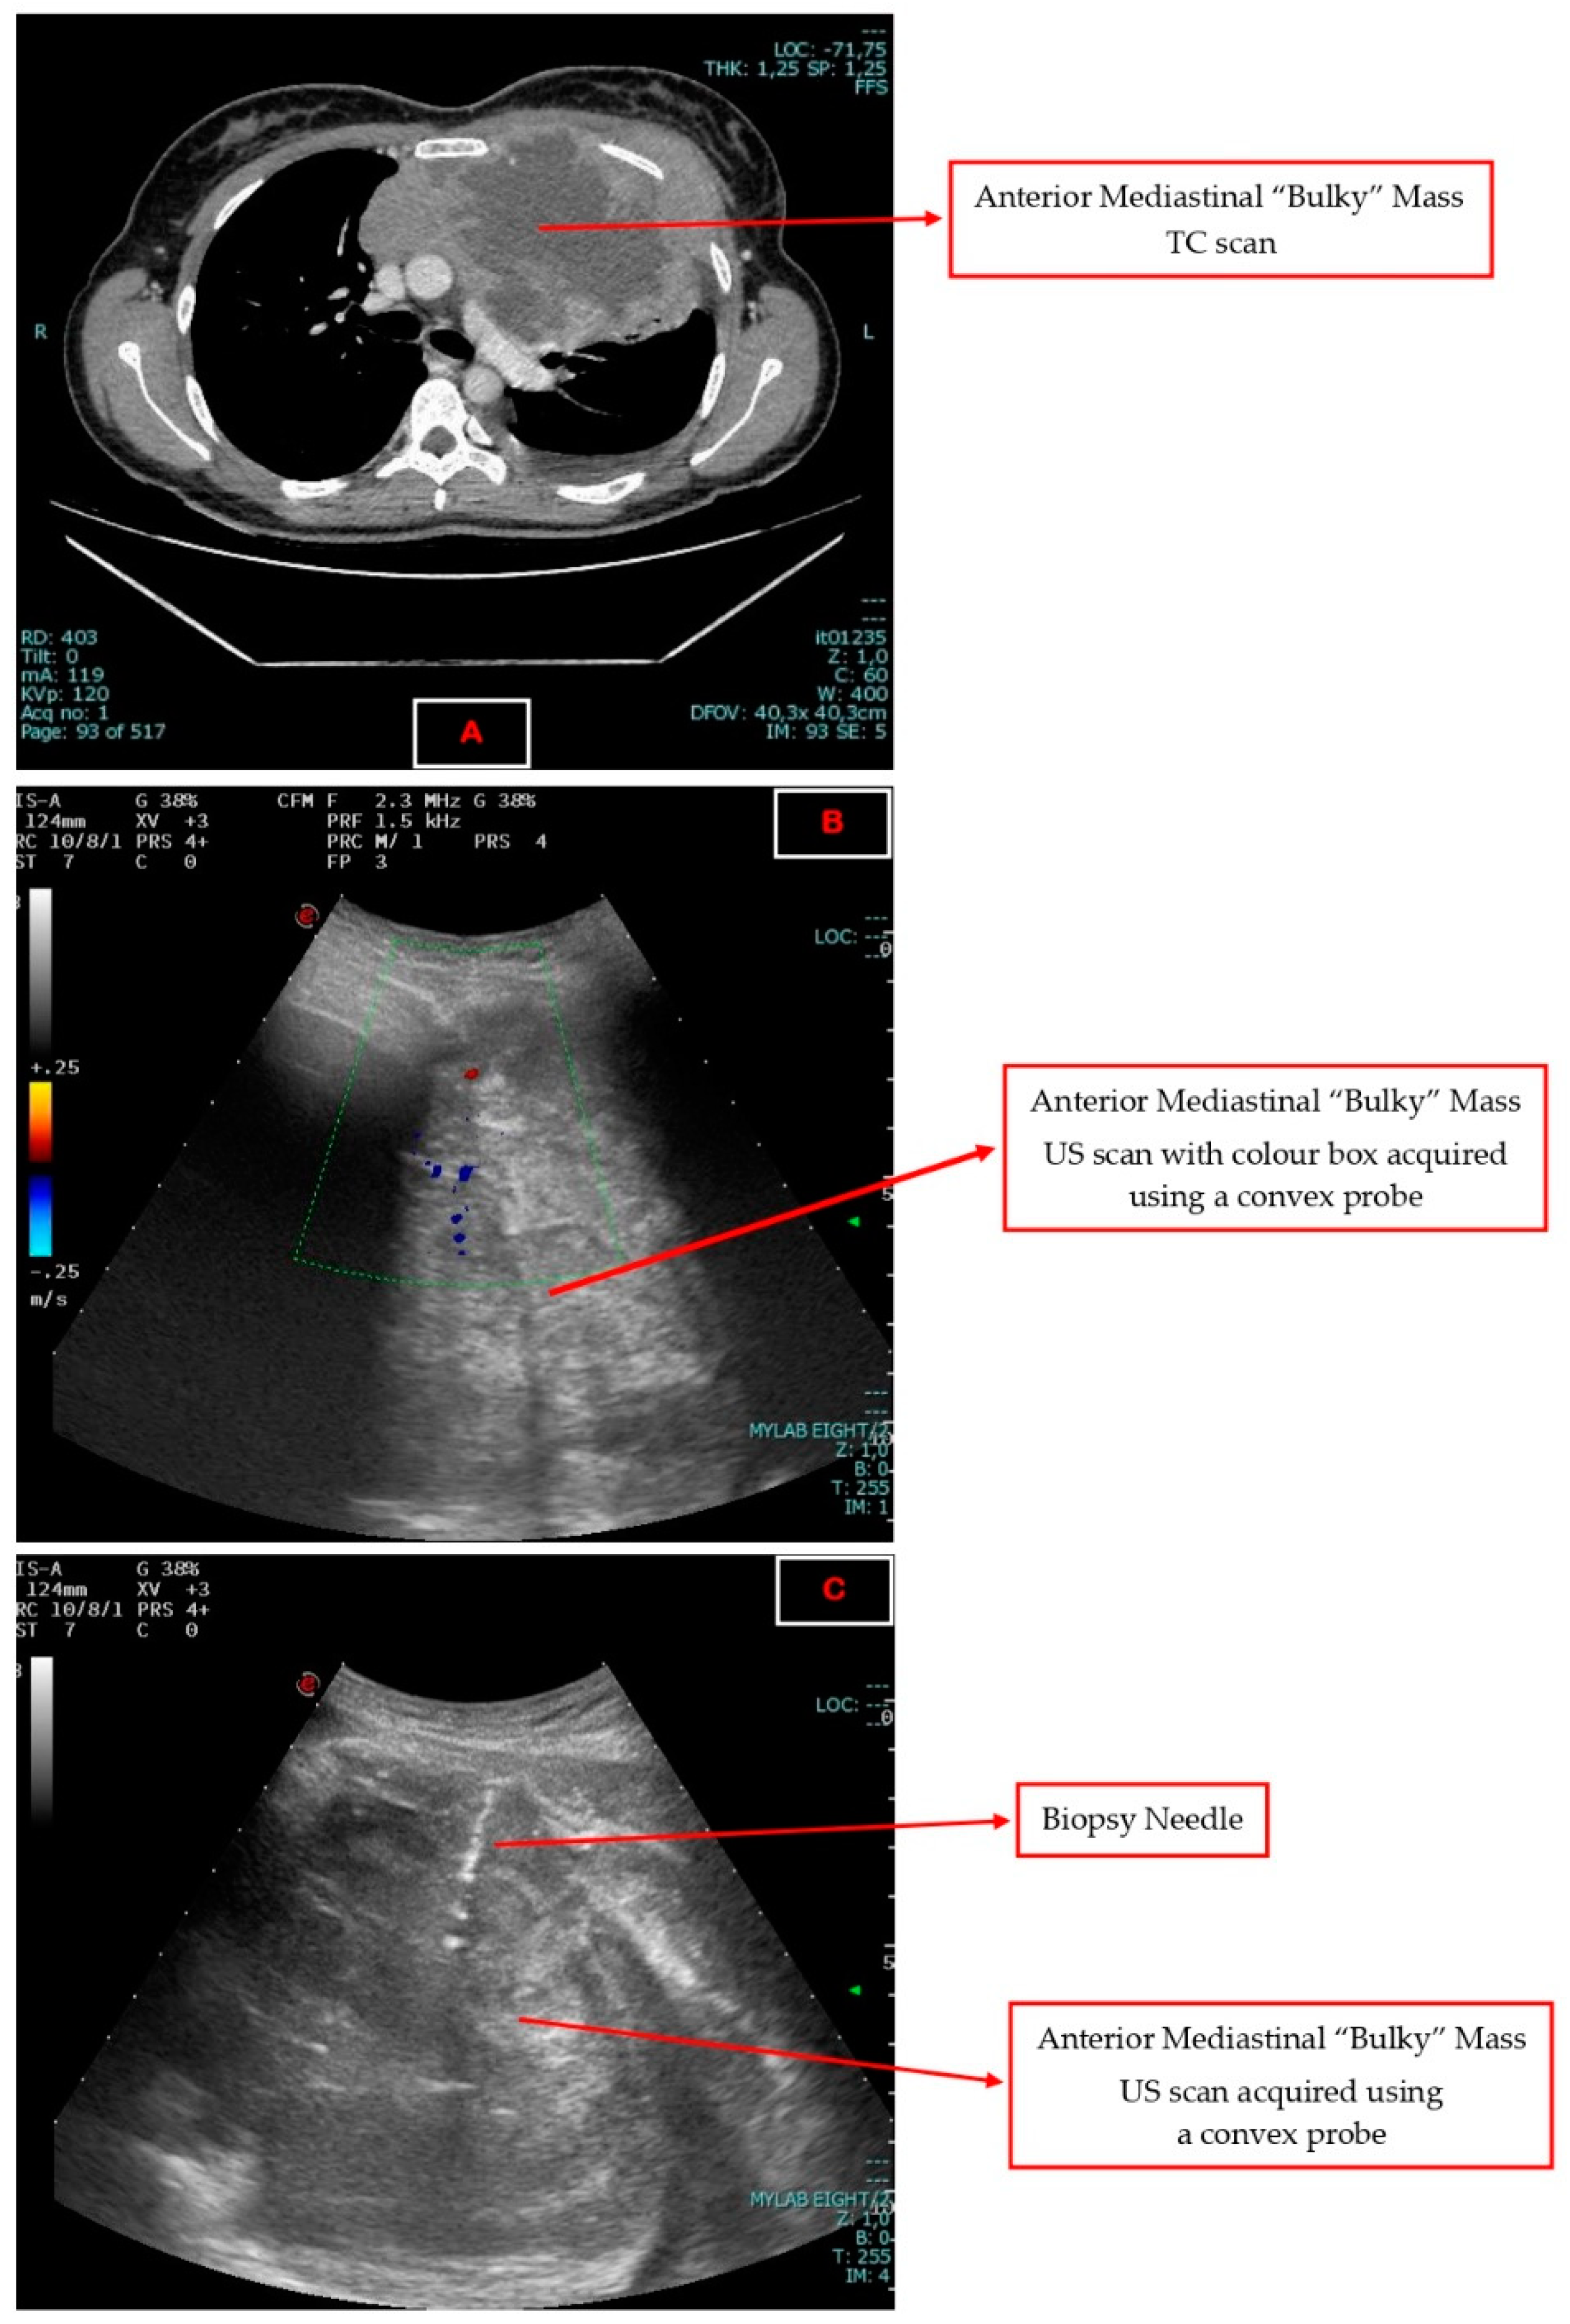

Ultrasound-Guided Needle Biopsy as an Alternative to Chamberlain’s Mediastinotomy and Video-Assisted Thoracoscopic Surgery (VATS) in the Diagnosis of Anterior Mediastinal Neoformations: A Retrospective Analysis

2. Materials and Methods